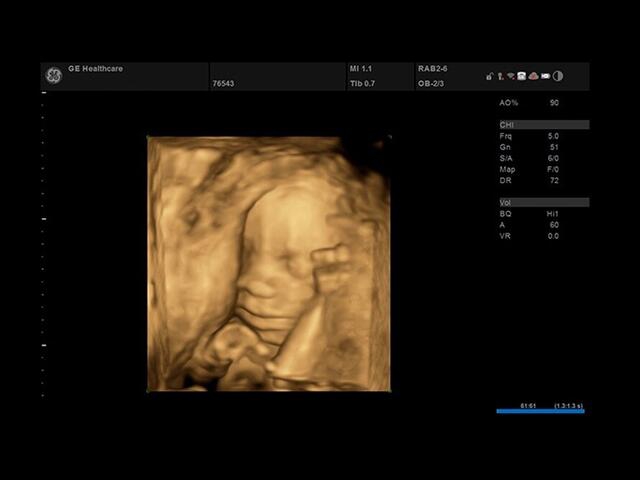

Ультразвуковой сканер GE Versana Essential отличается высокой точностью и мобильностью. Он широко используется при обследовании скелетно-мышечной системы и является незаменимым инструментом в урологии, гинекологии, педиатрии и общей радиологии.

Благодаря передовым технологиям и инновационным функциям, ультразвуковой сканер GE Versana Essential обеспечивает высокую четкость и детализацию получаемых изображений. Он позволяет врачам проводить диагностику и оценку состояния тканей и органов с высокой точностью, что способствует более точным и эффективным клиническим решениям.

• SonoBiometry : Эта функция позволяет быстро измерить биометрические параметры плода, такие как длина бедра, окружность головы, окружность живота и длина кости. Это важно для контроля развития плода и оценки его состояния.

• VOCAL : Это 3D-инструмент, который позволяет рассчитывать объем участков эксцентрической формы или сложных анатомических структур. Он полезен при анализе и измерении объемных образований внутри органов.